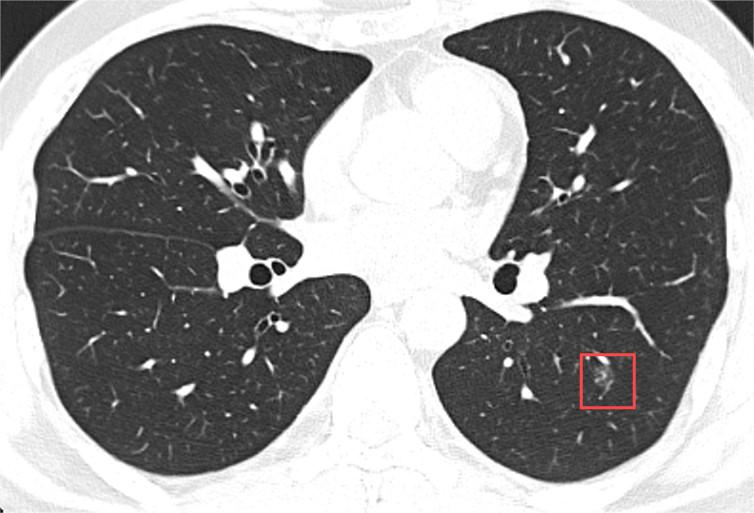

磨玻璃结节是指在肺部CT扫描上呈现为密度轻度增高、云雾状模糊影的结节状病灶。

它之所以得名“磨玻璃”,是因为这种病变区域的CT表现类似于磨砂玻璃,既非完全透明,也非完全不透明,而是介于两者之间的一种模糊状态。

磨玻璃结节的性质多样,既可以是良性的,如炎症、出血或局部纤维化,也可能是恶性的早期肺癌表现。研究表明,部分磨玻璃结节,特别是持续存在、体积增大或密度增高的GGN,具有较高的恶性转化风险,然而,这并不意味着所有GGN都会癌变,关键在于定期的监测与管理。

另外,磨玻璃结节的恶性风险与其大小、形态、密度变化及患者年龄、吸烟史等因素有关。